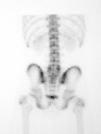

Als 15 dies el pacient es presenta amb simptomatologia atenuada. La GOP/SPECT (figs. 3 i 4) demostra fenòmens de remodelació òssia al nivell d'ambdues pars d'L5. Per tant, es conclou el diagnòstic d'espondilòlisi activa L5 dreta i espondilòlisi esquerra en formació. Es continua el mateix tractament i s'hi afegeix una pauta específica d'exercicis deslordosants i ortesis plantars de correcció.

Figura 3

Figura 4